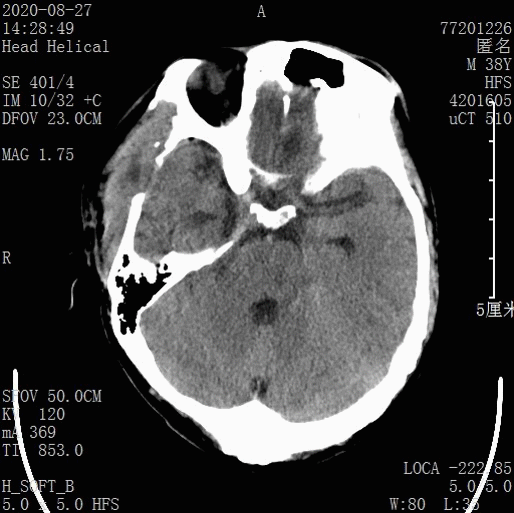

出院CT:

出院情况

患者搀扶可行走,对答切题,言语稍含糊。

查体:T:37.1℃,P:95次/分,R:18次/分,Bp:124/89mmHg,意识清醒,精神良好,GCS 14(E4V4M6),双侧瞳孔等大等圆,直径约2.0mm,光反应灵敏,右侧上眼睑下垂;视力、视野、听力粗测正常;颈抵抗阴性;双肺未闻及广泛湿罗音;心律齐,未闻及明显杂音;四肢自主活动;肌力查体合作欠佳;双侧巴氏征阴性。